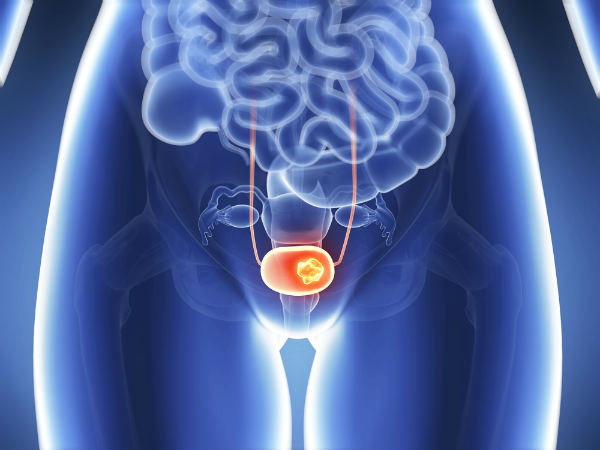

ଭୁବନେଶ୍ୱର,୧୮ା୯(ବ୍ୟୁରୋ): ଭାରତୀୟଙ୍କ ମଧ୍ୟରେ ବୃଦ୍ଧିପାଉଛି ବିନାଇନ୍ ପ୍ରୋଷ୍ଟାଟିକ୍ ହାଇପର୍ପ୍ଲାସିଆ(ବିପିଏଚ୍) ଜନିତ ସମସ୍ୟା। ମୂତ୍ରାଶୟର ବାହ୍ୟପଥରେ ବାଧା ସୃଷ୍ଟି କରୁଥିବା ବିପିଏଚ୍ ପ୍ରୋଷ୍ଟେଟ୍ ଏକ ବୟସ ସମ୍ବନ୍ଧିତ ରୋଗ ହୋଇଥିବାବେଳେ ବୟସ୍କ ପୁରୁଷଙ୍କ ମଧ୍ୟରେ ଏହା ଅଧିକ ଦେଖିବାକୁ ମିଳୁଛି। ଭାରତରେ ୪୫ ବର୍ଷରୁ ଅଧିକ ବୟସ୍କ ପ୍ରାୟ ୬୫% ପୁରୁଷ ଏଭଳି ସମସ୍ୟାର ସମ୍ମୁଖୀନ ହୋଇଥାନ୍ତି। ତେବେ ଅଧିକାଂଶ ପୁରୁଷ ପ୍ରାଥମିକ ଅବସ୍ଥାରେ ଏହାକୁ ଲୁଚାଉଥିବାରୁ ପରବର୍ତ୍ତୀ ସମୟରେ ଏହା ମାରାତ୍ମକ ସାବ୍ୟସ୍ତ ହେଉଥିବା ଦେଖିବାକୁ ମିଳୁଛି। ବୟସ୍କ ପୁରୁଷ ସଂଖ୍ୟାରେ ଭାରତ ହେଉଛି ବିଶ୍ୱର ସର୍ବବୃହତ୍ ରାଷ୍ଟ୍ର। ଏଥିସହ ଏଠାରେ ମଧ୍ୟ ବୟସ୍କ ପୁରୁଷଙ୍କ ସଂଖ୍ୟା ଦ୍ରୁତ ବୃଦ୍ଧି ପାଉଛି। ଏହି ଶ୍ରେଣୀର ପୁରୁଷମାନେ ସାଧାରଣତଃ ଟାଇପ୍-୨ ଡାଇବେଟିସ୍, ଉଚ୍ଚ ରକ୍ତଚାପ, କୋଲେଷ୍ଟେରୋଲ, କାଟାରାକ୍ଟ ଏବଂ ବିନାଇନ୍ ପ୍ରୋଷ୍ଟାଟିକ୍ ହାଇପର୍ପ୍ଲାସିଆ ତଥା ବିପିଏଚ୍ ଦ୍ୱାରା ସୃଷ୍ଟି ହେଉଥିବା ଏକାଧିକ ଅସୁସ୍ଥତାର ସମ୍ମୁଖୀନ ହୋଇଥାନ୍ତି। ବିପିଏଚ୍ର ଆକ୍ରାନ୍ତ ପୁରୁଷମାନେ ବାରମ୍ବାର ପରିସ୍ରା ଲାଗିବା, ରାତିରେ ଶୋଇବା ସମୟରେ ପରିସ୍ରା ପାଇଁ ବାରମ୍ବାର ନିଦରୁ ଉଠିବା, ପରିସ୍ରା ସମୟରେ ଦୁର୍ବଳ ପ୍ରବାହ ଓ ପରିସ୍ରା ପରେ ମଧ୍ୟ ସନ୍ତୁଷ୍ଟ ନଲାଗିବା ଭଳି ସମସ୍ୟା ଭୋଗିଥାନ୍ତି ବୋଲି ଭିଏସ୍ଏସ୍ ମେଡିକାଲ କଲେଜ ସମ୍ବଲପୁର୍ର ୟୁରୋଲୋଜିଷ୍ଟ ଡା. ସଞ୍ଜୟ ମହାପାତ୍ର କହିଛନ୍ତି।

ପ୍ରୋଷ୍ଟେଟ୍ ସଚେତନତା ମାସ ଅବସରରେ ଆୟୋଜିତ ଏକ ୱେବିନାର୍ରେ ସୂଚନା ଦେଇ ଡା. ମହାପାତ୍ର କହିଛନ୍ତି, ବିପିଏଚ୍ ଆକ୍ରାନ୍ତ ଅଧିକାଂଶ ରୋଗୀ ନିଜକୁ ସ୍ବାଭାବିକ ଦର୍ଶାଇଥାନ୍ତି। ସେମାନେ ଚୁପ୍ଚାପ୍ ଏହି ଲକ୍ଷଣଗୁଡିକୁ ସହ୍ୟ କରିଥାନ୍ତି ଓ ସ୍ବାସ୍ଥ୍ୟାବସ୍ଥା ଜଟିଳ ନ ହେବା ପର୍ଯ୍ୟନ୍ତ ତାହାର ମୁକାବିଲା ପାଇଁ ବିଭିନ୍ନ ବିକଳ୍ପ ଆପଣାଇଥାନ୍ତି। ମାତ୍ର ଠିକ୍ ସମୟରେ ଏହାର ଚିକିତ୍ସା କରା ନ ଗଲେ ଏହା ଘାତକ ସାବ୍ୟସ୍ତ ହୋଇଥାଏ। ରିକରେଣ୍ଟ୍ ଆକ୍ୟୁଟ୍ ୟୁରିନାରି ରିଟେନ୍ଶନ(ପରିସ୍ରା କରିବାରେ ହଠାତ୍ ଯନ୍ତ୍ରଣାଦାୟକ ଅସାମର୍ଥତା), ରିକରେଣ୍ଟ୍ ୟୁରିନାରି ଇନ୍ଫେକ୍ସନ, ଷ୍ଟୋନ୍ ହେବା, ଏପରିକି ଉଭୟ କିଡ୍ନି କ୍ଷତିଗ୍ରସ୍ତ କିମ୍ବା ଫେଲ୍ ହେବା ଭଳି ସମସ୍ୟା ସୃଷ୍ଟି ହୋଇଥାଏ। ଅଧିକାଂଶ ମାମଲାରେ ସର୍ଜରୀ ପରେ ମଧ୍ୟ ସମସ୍ୟା କମି ନ ଥାଏ। ଫଳରେ ରୋଗୀଙ୍କୁ ସାରା ଜୀବନ କ୍ୟାଥେଟେରିଜେଶନ କିମ୍ବା ଡାଇଲିସିସ୍ରେ ରଖିବାକୁ ପଡିପାରେ। ଶାରୀରିକ ଲକ୍ଷଣ କିମ୍ବା ରେଡିଓଗ୍ରାଫିକ୍ ପରୀକ୍ଷଣ ଓ କିଛି ଲ୍ୟାବ୍ ଟେଷ୍ଟରୁ ବିପିଏଚ୍ ଚିହ୍ନଟ କରାଯାଇଥାଏ। ତେବେ ସୁସ୍ଥ ଜୀବନଶୈଳୀ ଓ ଅଭ୍ୟାସକୁ ଆପଣାଇବା ଓ କମ୍ ଔଷଧ ସେବନ କରି ବିପିଏଚ୍କୁ ଭଲ କରାଯାଇପାରିବ। ଲକ୍ଷଣଗୁଡିକ ଅନିୟନ୍ତ୍ରିତ ହେଲେ କିମ୍ବା ସ୍ବାସ୍ଥ୍ୟାବସ୍ଥା ଜଟିଳ ହେଲେ ପ୍ରୋଷ୍ଟାଟିକ୍ ଟିସୁକୁ ସର୍ଜରୀ ମାଧ୍ୟମରେ ବାହାର କରିବା ଜରୁରୀ ହୋଇଥାଏ ବୋଲି ଡା. ମହାପାତ୍ର କହିଛନ୍ତି।